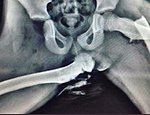

Στη συνέχεια αντικαταστάθηκαν με πιο φθηνούς που ήταν διαθέσιμοι στην αγορά οι οποίοι όμως όταν χρειάστηκε να ενεργοποιηθούν εκτόξευσαν μεταλλικά θραύσματα στο στήθος, τον λαιμό και τα μάτια των οδηγών, σε ατυχήματα που θα μπορούσαν να επιβιώσουν χωρίς να τραυματιστούν.